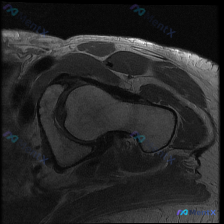

肩关节MRI单T1序列示盂唇、肩胛下肌腱信号不均,下一步该怎么看?

- 扫描序列:肩关节轴位T1加权图像

- 主要发现:

- 肩胛下肌腱附着处信号略有不均,前方间隙软组织信号紊乱

- 盂唇形态尚完整,但T1序列对病变评估有局限

- 未见典型Hill-Sachs损伤、肩峰下撞击征象

- 单T1序列下,如何解读肩胛下肌腱的信号改变?

- 盂唇病变的可能性有多大?

- 下一步需要补充哪些影像序列?

- 结合临床,这些发现最可能提示什么?